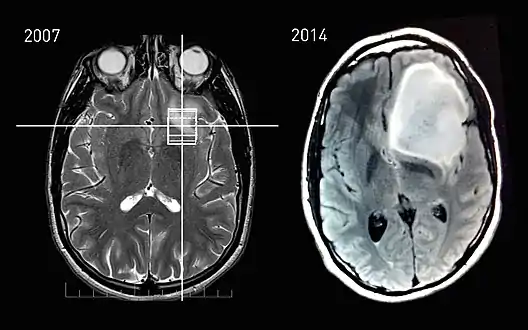

MRI scans of a patient with astrocytoma, showing the tumor's progression between the incidental finding in 2007 and the onset of phenotypical changes in 2014.

Tumor progression is the third and last phase in tumor development.[1] This phase is characterised by increased growth speed and invasiveness of the tumor cells. As a result of the progression, phenotypical changes occur and the tumor becomes more aggressive and acquires greater malignant potential. Together with the progression, more and more aneuploidy occurs. This may be evident as nuclear polymorphism.